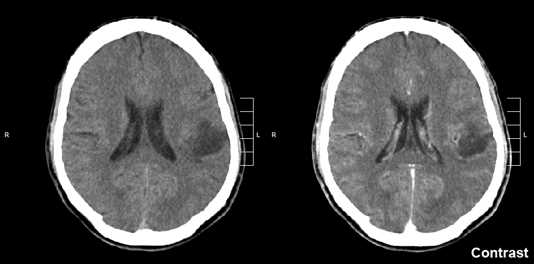

Images of glioma in the left parietal lobe (brain CT scan), WHO grade 2.Fig.1 Glioma in the left parietal lobe (brain CT scan), WHO grade 2. Distributed under CC BY-SA 3.0, from Wiki, without modification.